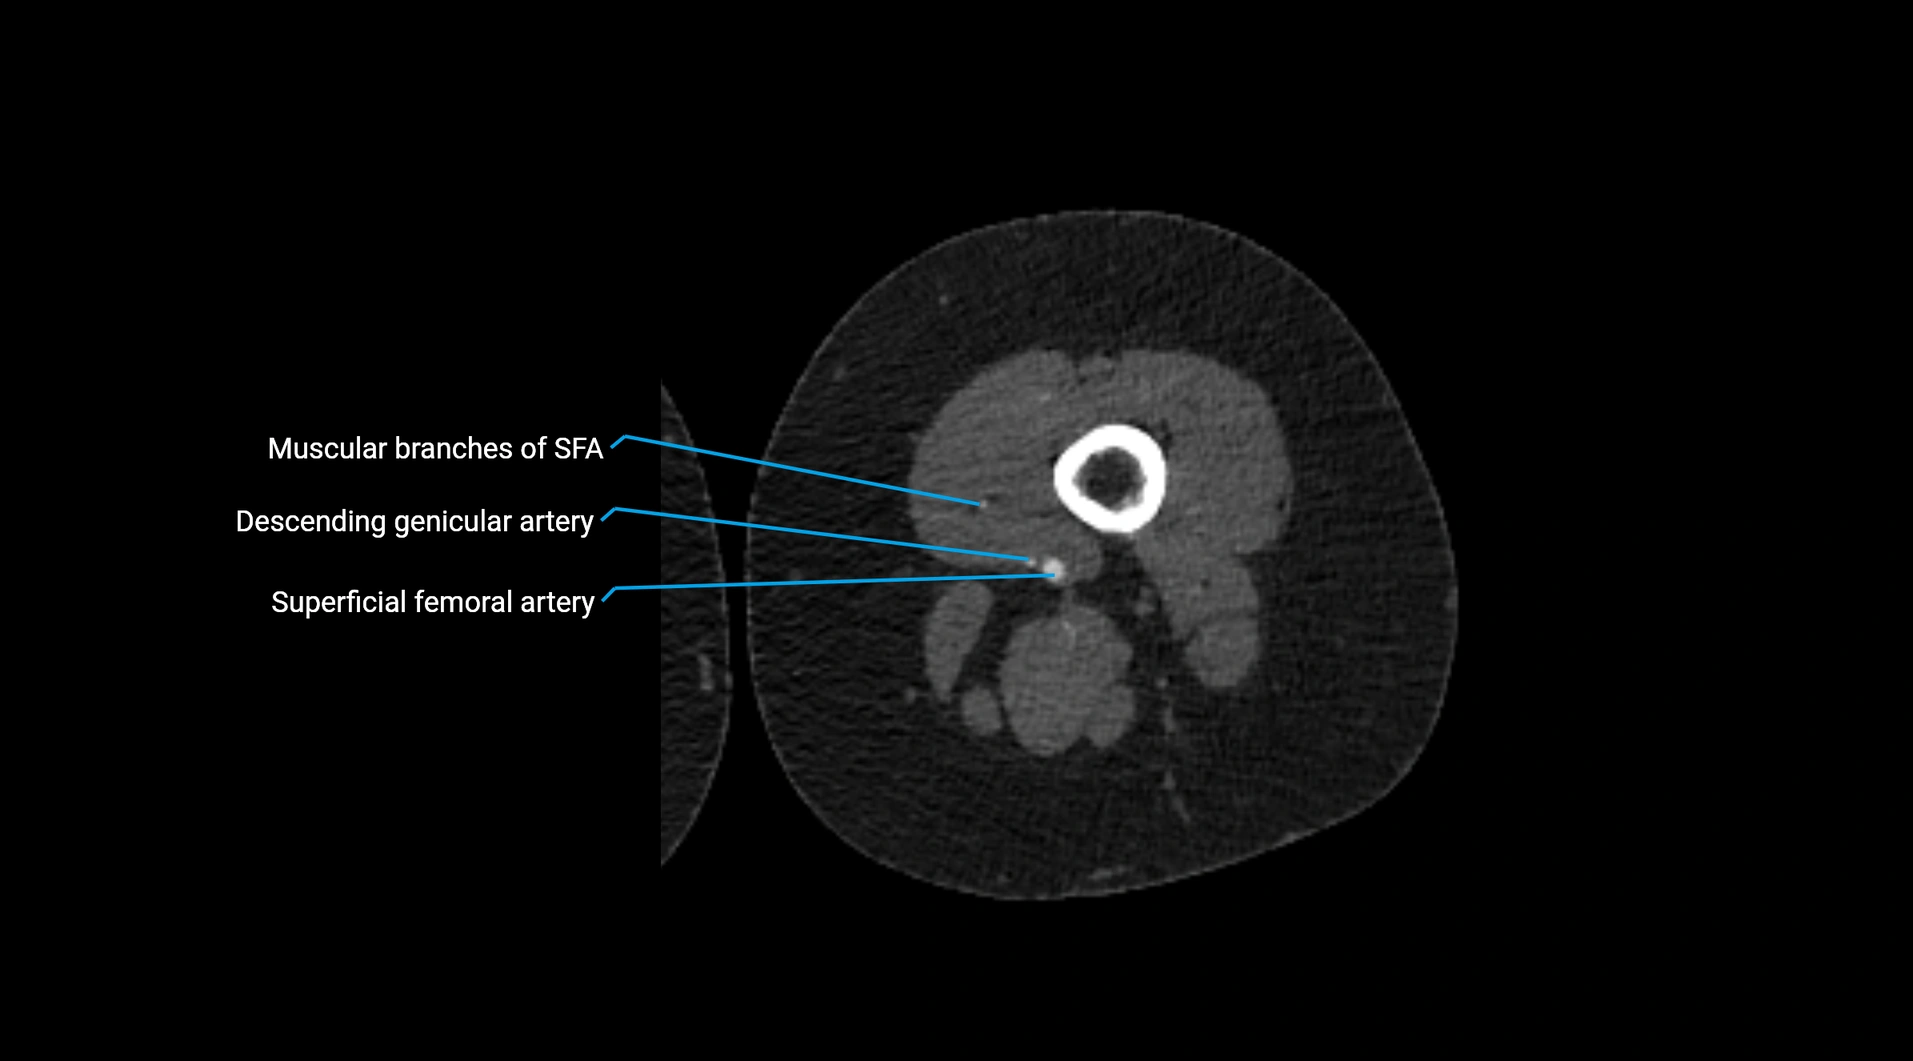

Contrast-enhanced CT (CTA):

• Gold standard for abdominal aortic imaging

• Provides excellent detail of lumen, wall, aneurysm, thrombus, and branch vessels

• Multiplanar and 3D reconstructions help in aneurysm measurement, stent graft planning, and dissection evaluation

• Detects acute rupture, traumatic injury, or occlusion with high sensitivity